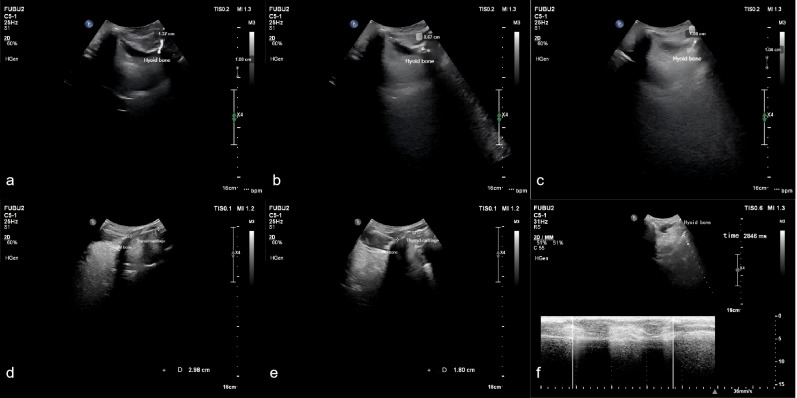

Methods: This study included 46 stroke patients with pharyngeal dysphagia, diagnosed via videofluoroscopic swallowing study (VFSS), and treated at the Department of Rehabilitation Medicine, Affiliated Brain Hospital of Nanjing Medical University (June 2020-August 2024). Swallowing function was assessed using seven pharyngeal phase parameters from the Videofluoroscopic Dysphagia Scale (VDS) at baseline and post-rehabilitation. Patients were stratified into favorable (n = 26) and unfavorable (n = 20) prognosis groups based on post-treatment VDS and Functional Oral Intake Scale (FOIS) scores. Submental B/M-mode ultrasonography quantified hyoid bone displacement parameters pre- and post-rehabilitation, including maximum displacement, anterior displacement, superior displacement, total movement duration, and hyoid-thyroid cartilage approximation ratio (ASR).

Result: No significant differences were observed between groups in baseline characteristics. Post-treatment, the favorable group showed significantly lower Rosenbek scores (p = 0.000), reduced VDS scores (p = 0.000), and decreased feeding tube dependency (p = 0.000). Post-treatment, the favorable group exhibited greater anterior displacement (p = 0.011), higher ASR (p = 0.000), and shorter total movement duration (p = 0.005). Logistic regression identified hyoid anterior displacement (odds ratio (OR) = 9.539, p = 0.011) and ASR (OR = 14.238, p = 0.001) as independent prognostic predictors. ROC curve analysis indicated that hyoid anterior displacement (area under the curve (AUC) = 0.720) and ASR (AUC = 0.816) were significant discriminators of favorable outcomes, with optimal cutoff values of 0.865 cm (92.3% sensitivity, 50.0% specificity) and 31.5% (84.6% sensitivity, 65.0% specificity), respectively. The combined model further improved predictive accuracy (AUC = 0.854, 84.6% sensitivity, 85.0% specificity).